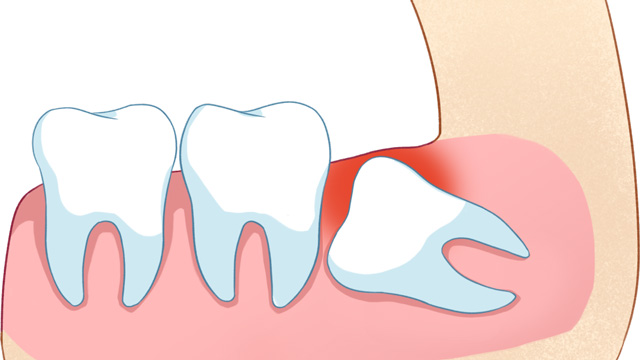

01智齿挤压邻牙,导致牙齿拥挤/移位

这是最常见的拔除原因。正畸的核心需求之一一般是“排齐拥挤牙齿”,而智齿作为口腔中最后萌出的牙齿(通常在20岁左右萌出),由于生长位置特殊、空间有限,很可能会持续挤压旁边的第二磨牙,导致第二磨牙倾斜、移位,进而引发整个牙列拥挤。

如果不拔除这颗“肇事智齿”,即使通过正畸排齐了牙齿,后期也会因为智齿的持续挤压,导致牙齿再次拥挤、反弹。

有些智齿虽然目前没有疼痛、没有挤压邻牙,但拍X光片后发现,它属于“埋伏阻生”(完全埋在牙龈下),或者生长方向异常,未来很可能会萌出、挤压邻牙,甚至引发囊肿、肿瘤等问题。对于这类堪比“定时炸弹”的智齿,医生通常会建议拔除,避免后续出现更严重的口腔问题。